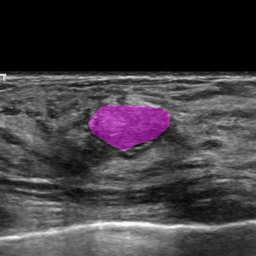

Refer to caption

Figure 1: A malignant lesion in breast ultrasound

Breast lesion segmentation is very challenging, especially when there is the presence of noise, the ill-defined edges, irregular shapes, and different posterior behaviors of lesions. As Fig. 1 shows, there is strong shadowing in the posterior and upper region, the lesion boundary is fuzzy and not clear. Therefore, there is a risk that segmentation algorithms fail, causing oversegmentation.